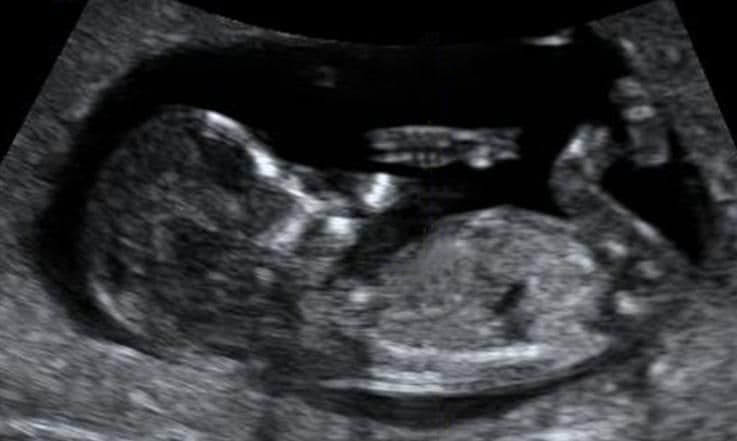

Your baby is starting to swallow amniotic fluid more regularly: this enters the stomach (seen here as a dark circle in the centre of the abdomen). The tiny bladder is also visible as a black fluid-filled structure within the lower pelvis.